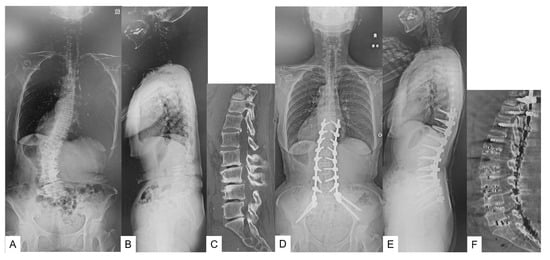

The patient underwent T10-pelvis fixation because of low back pain and gait disturbance (Figure 6).

Figure 6. 72-year-old woman, adult spinal deformity, T10 pelvis fixation. (A): Preoperative anteroposterior radiogram, (B): Preoperative lateral radiogram (sagittal vertical axis 83 mm, lumbar lordosis 7 degrees, pelvic tilt 39 degrees), (C): Preoperative CT, (D): Postoperative anteroposterior radiogram, (E): Postoperative anteroposterior radiogram (sagittal vertical axis 0 mm, lumbar lordosis 46 degrees, pelvic tilt 24 degrees), (F): Postoperative CT.